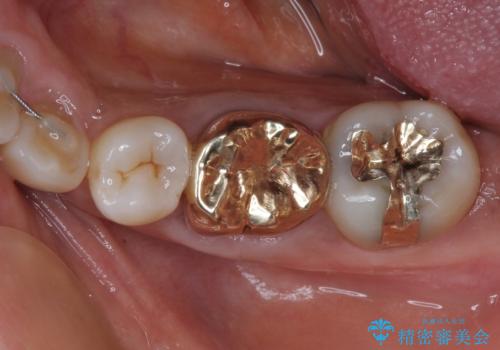

ゴールドは「白い歯」ではありませんが、銀歯の金属色とは異なり、非常にきれいな色合いが特徴です。

もちろん、適合が極めて良いという圧倒的メリットもゴールドクラウンやゴールドインレーの特徴です。